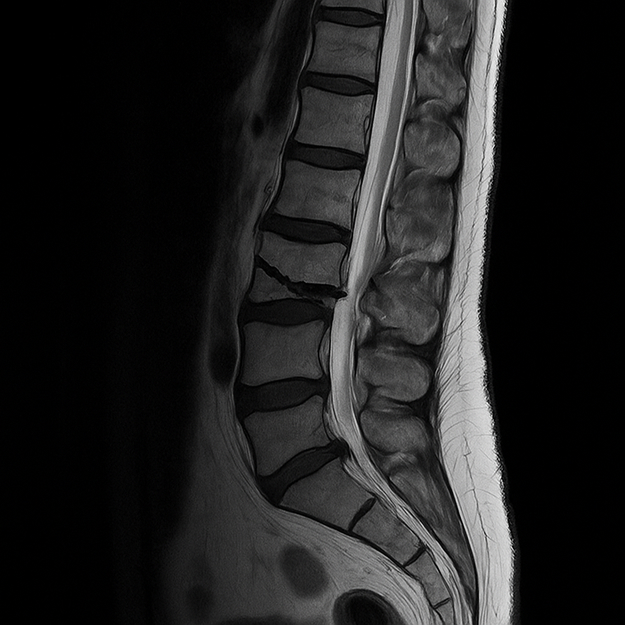

- Спиральная компьютерная томография. На снимке видны костные фрагменты, повреждения дужек, тел позвонков, в том числе их количество, а также в целом удается определить уровень перелома.

- Магнитно-резонансная томография необходима для подтверждения диагноза, если предыдущие методы оказались недостаточно информативными.